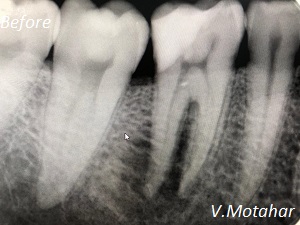

Root Canal Treatment on a molar tooth!

before

after